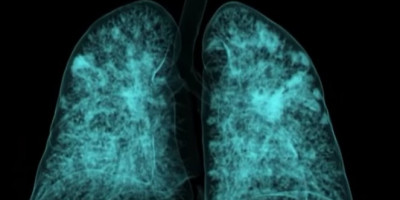

Kako izgleda snimak kovid pacijenata

Kada se pogleda snimak kovid pacijenata slika je podeljena na tipičnu i atipičnu.

- Najčešće se radi o virusnoj pneumoniji koja se javlja obostrano na plućima i to najčešće u donjim delovima, pozadi. To su najčešće kao mlečno staklo, jedna opna sa tankim septama i to je neki početni nivo. Kasnije dolazi do zadebljanja tkiva pluća odnosno intersticijuma - ističe Banko i dodaje da "kako odmiču dani, važno je reći da su samo dani u pitanju, intersticijum se zadebljava, stvaraju se zone konsolidacije i tamo negde posle 12, 13 dana i ožiljne fibrozne zone koje se ne mogu reparirati".

Objasnio je i koliko se brzo razvijaju promene.

- Prvih tri do četiri dana to je ta početna faza kada mogu biti samo vrlo diskretne promene na plućima ili ih uopšte ne mora biti. U toj nekoj fazi od četvrtog, petog dana do osmog stvaraju se ta mlečna stakla, počinju te zone konsolidacije. Ako pacijent ne počne sa simptomatskom terapijom, odnosno terapijom koja se daje da pomogne našem imunom sistemu da se izbori sa time, onda od devetog do 13. dana imamo ozbiljne ožiljne zone, izraženu konsolidaciju odnosno zgrušavanje tkiva pluća, a posle 14. dana i fibrozu pluća što je zapravo krajnji stadijum te bolesti - rekao je Banko.